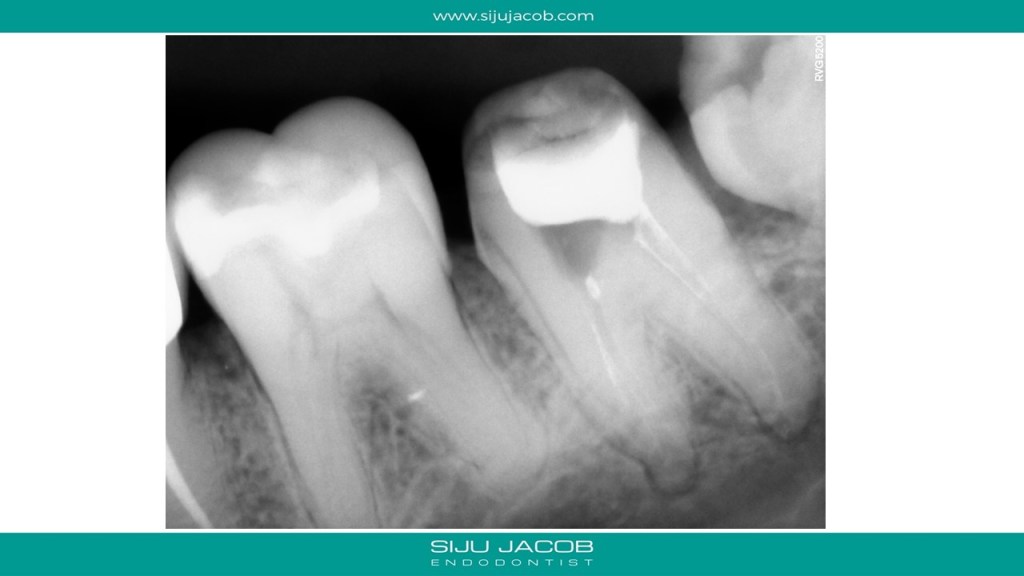

This patient had pain after endo and crown on a mandibular second molar. She went back to the practitioner who removed the crown and removed the old gutta percha. The tooth subsequently flared up and she landed in my office. I found a missed middle mesial. We put the tooth on long-term calcium hydroxide intra canal medication, extracted the wisdom tooth and waited for the tenderness to subside before obturation . Pictures are self-explanatory